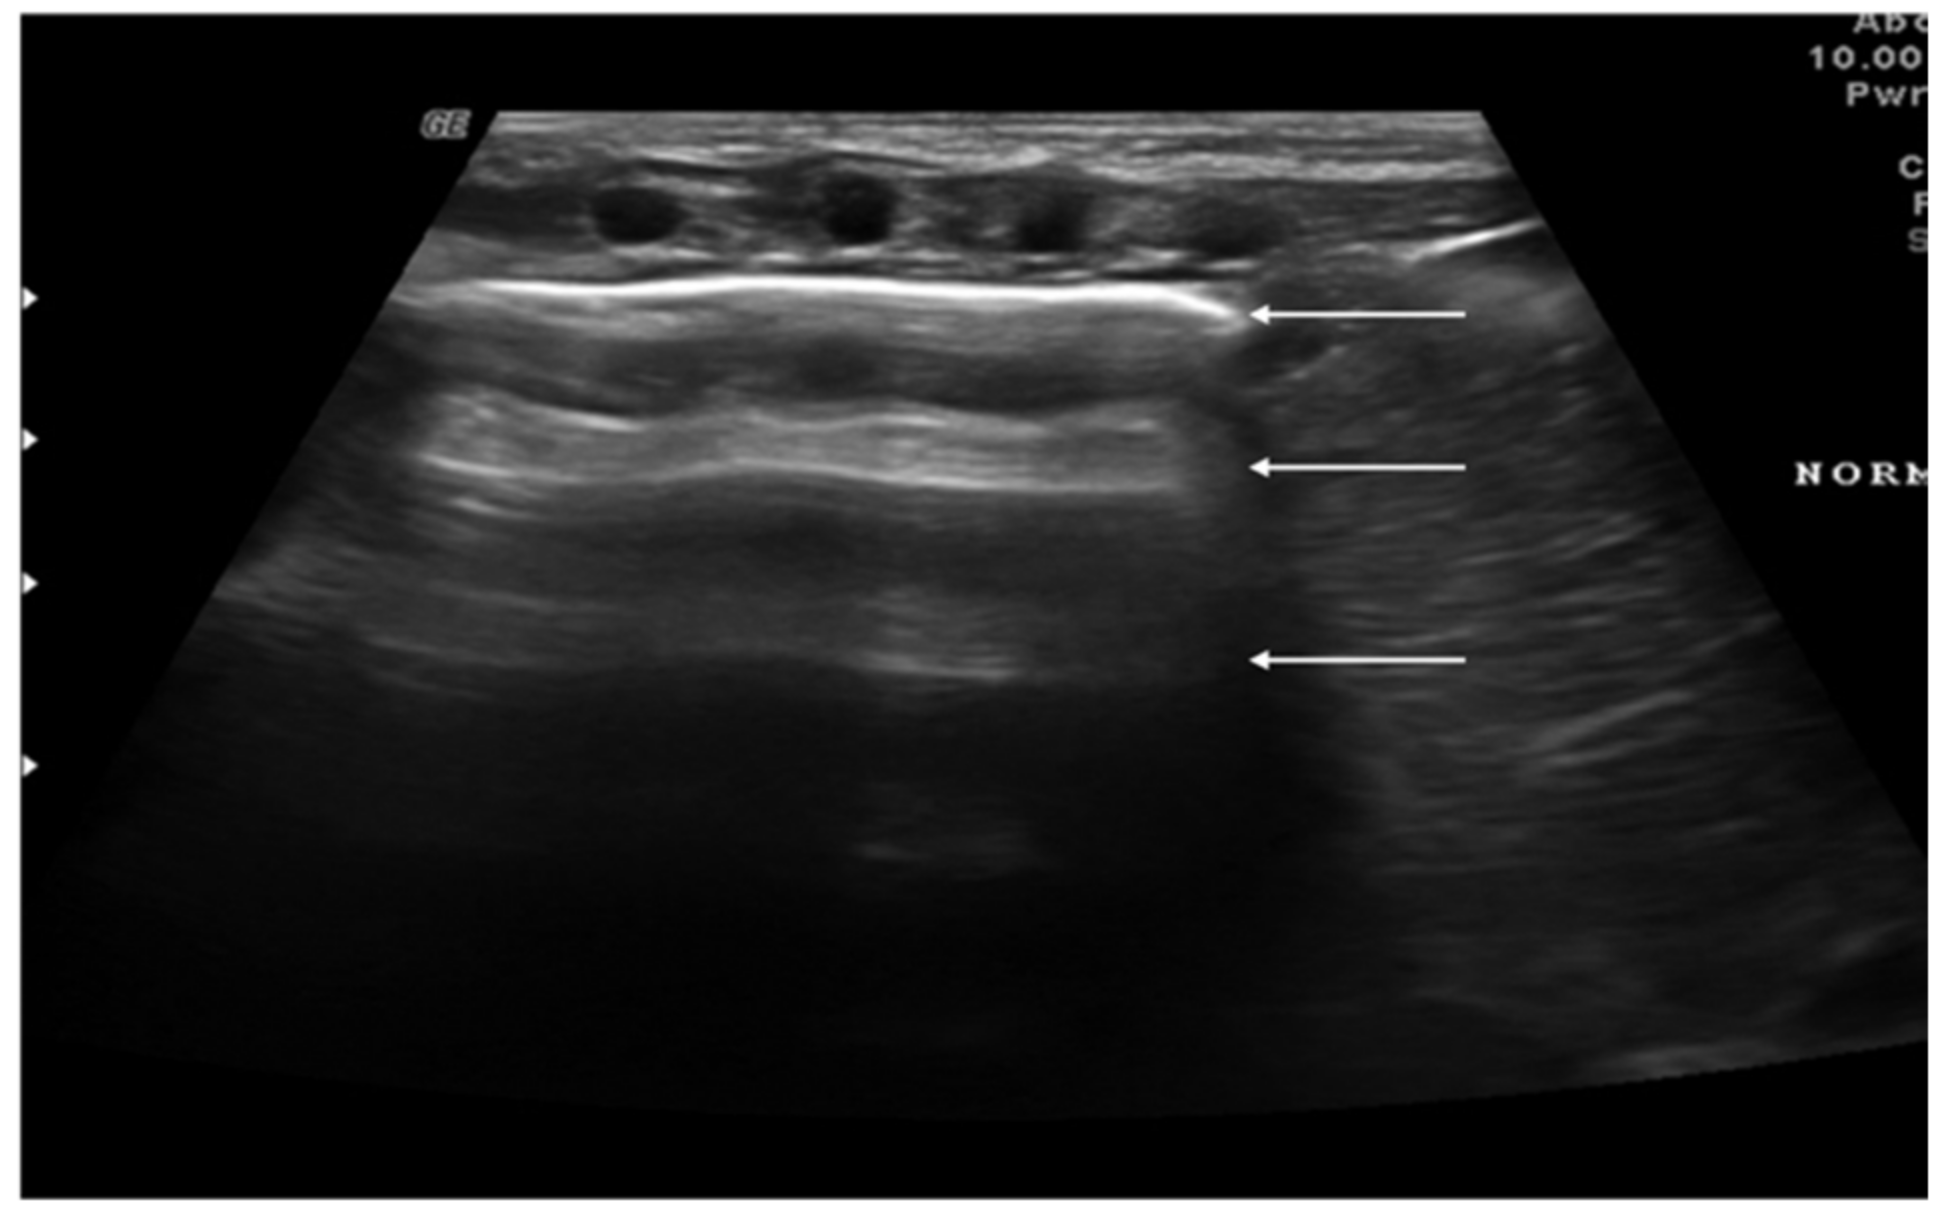

The role of LUS in identifying pleural effusion is also well established [53]. In fact, many studies have evaluated the efficacy of lung ultrasound in the diagnosis of pleural effusion, calculating its sensitivity and specificity, which have often been close to 100% [54]. These studies have confirmed the superiority of ultrasound over CXR in pleural effusion detection due to the capability of ultrasound to detect fluid collections as small as 20 mL [55]. Usually, pleural effusion can be visualized by ultrasound as a dark and anechogenic region located above the diaphragm that also determines the disappearance of the mirror image of the liver and spleen in the lung fields, which can be visualized in the healthy lung (Figure 10) [14]. Ultrasound also allows quantifying the amount of fluid accumulated in the pleural cavity well and characterizing the fluid collection differentiating a transudate from an exudate. The transudate is characterized by a dark image without internal echoes, representing an uncomplicated collection, while an image characterized by a septate or multiloculated corpuscular fluid collection is typical of the exudate [14].

Figure 10. Anechogenic fluid collection above the diaphragm suggestive of pleural effusion (white arrows).